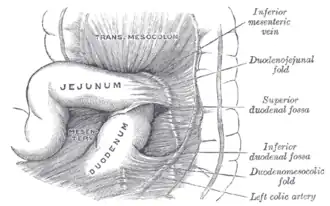

The jejunum lies between the duodenum and the ileum and is considered to start at the suspensory muscle of the duodenum, a location called the duodenojejunal flexure.[4] The division between the jejunum and ileum is not anatomically distinct.[5] In adult humans, the small intestine is usually 6–7 m (20–23 ft) long (post mortem), about two-fifths of which (about 2.5 m (8.2 ft)) is the jejunum.[4]